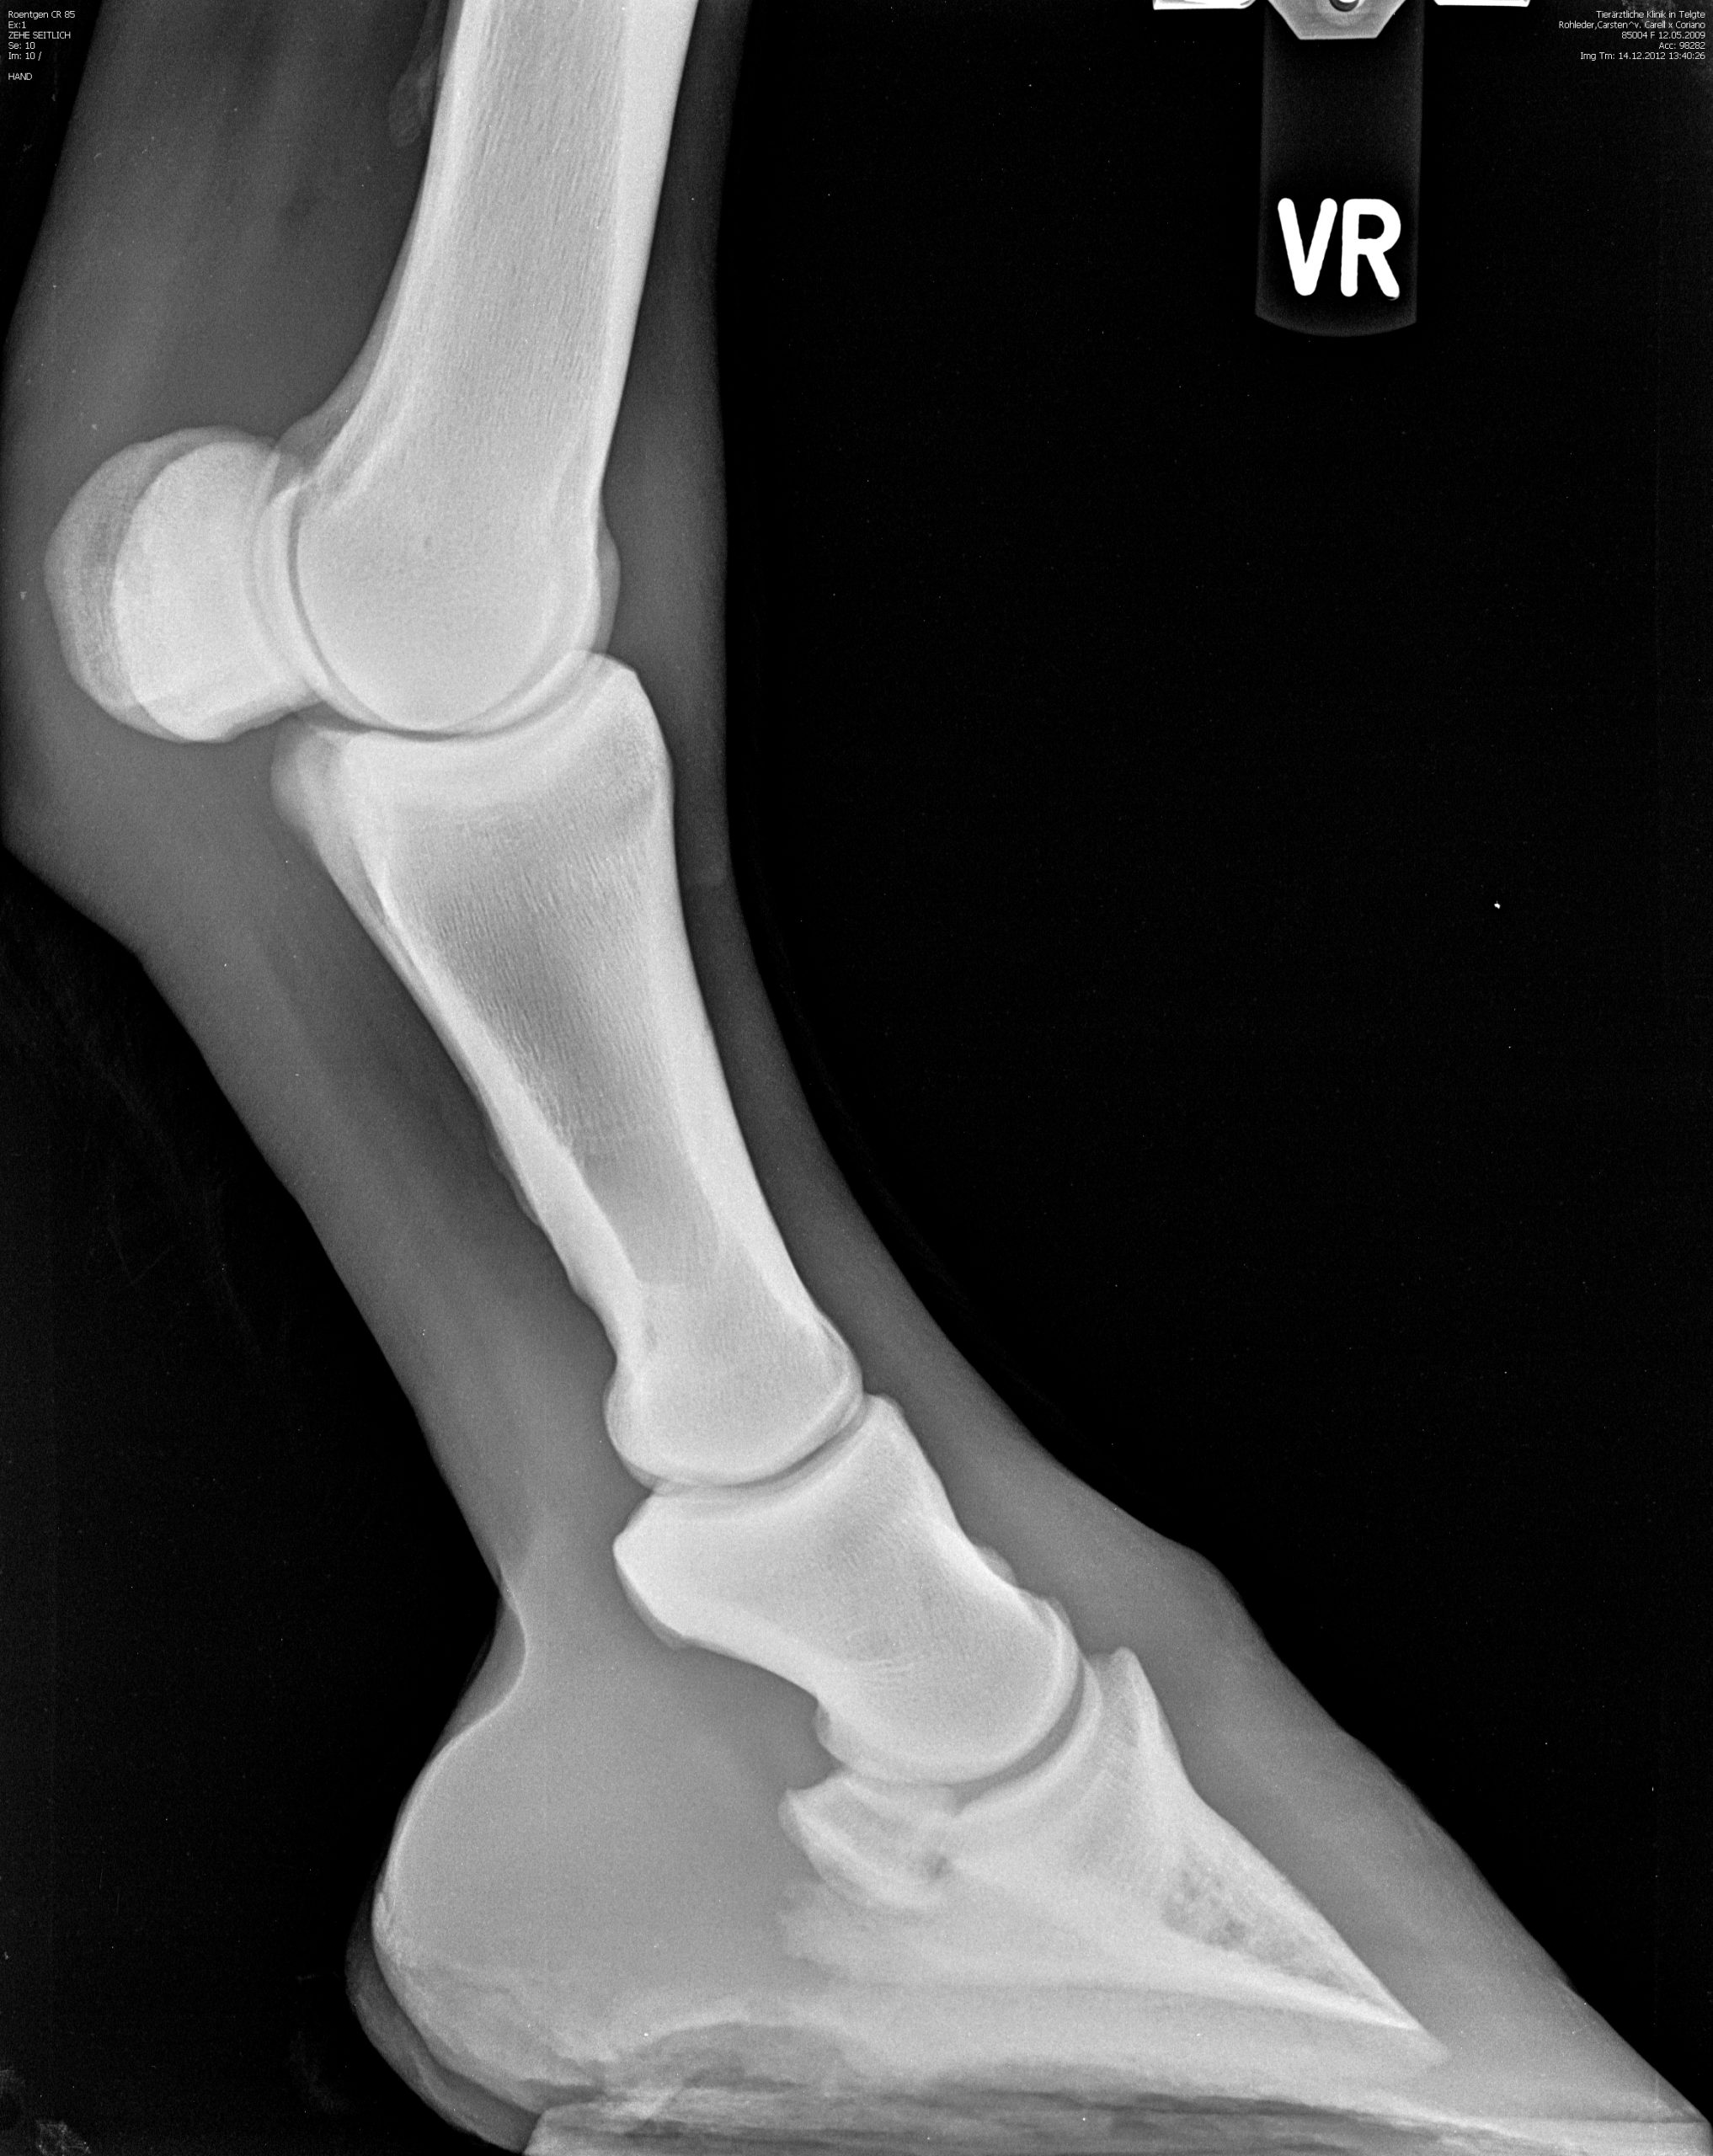

Röntgenaufnahme einer Pfote

Röntgenbilder

Diese Sammlung zeigt verschiedene Röntgenaufnahmen, die eine Vielzahl von anatomischen Strukturen und potenziellen Gesundheitszuständen veranschaulichen. Jede Aufnahme bietet wertvolle Einblicke in die Gesundheit und das Wohlbefinden Ihrer Pferde.